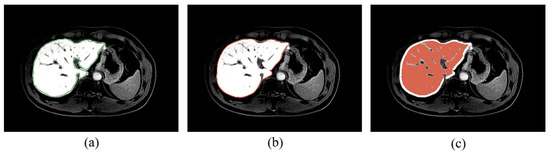

2.5.1. ROI Extraction